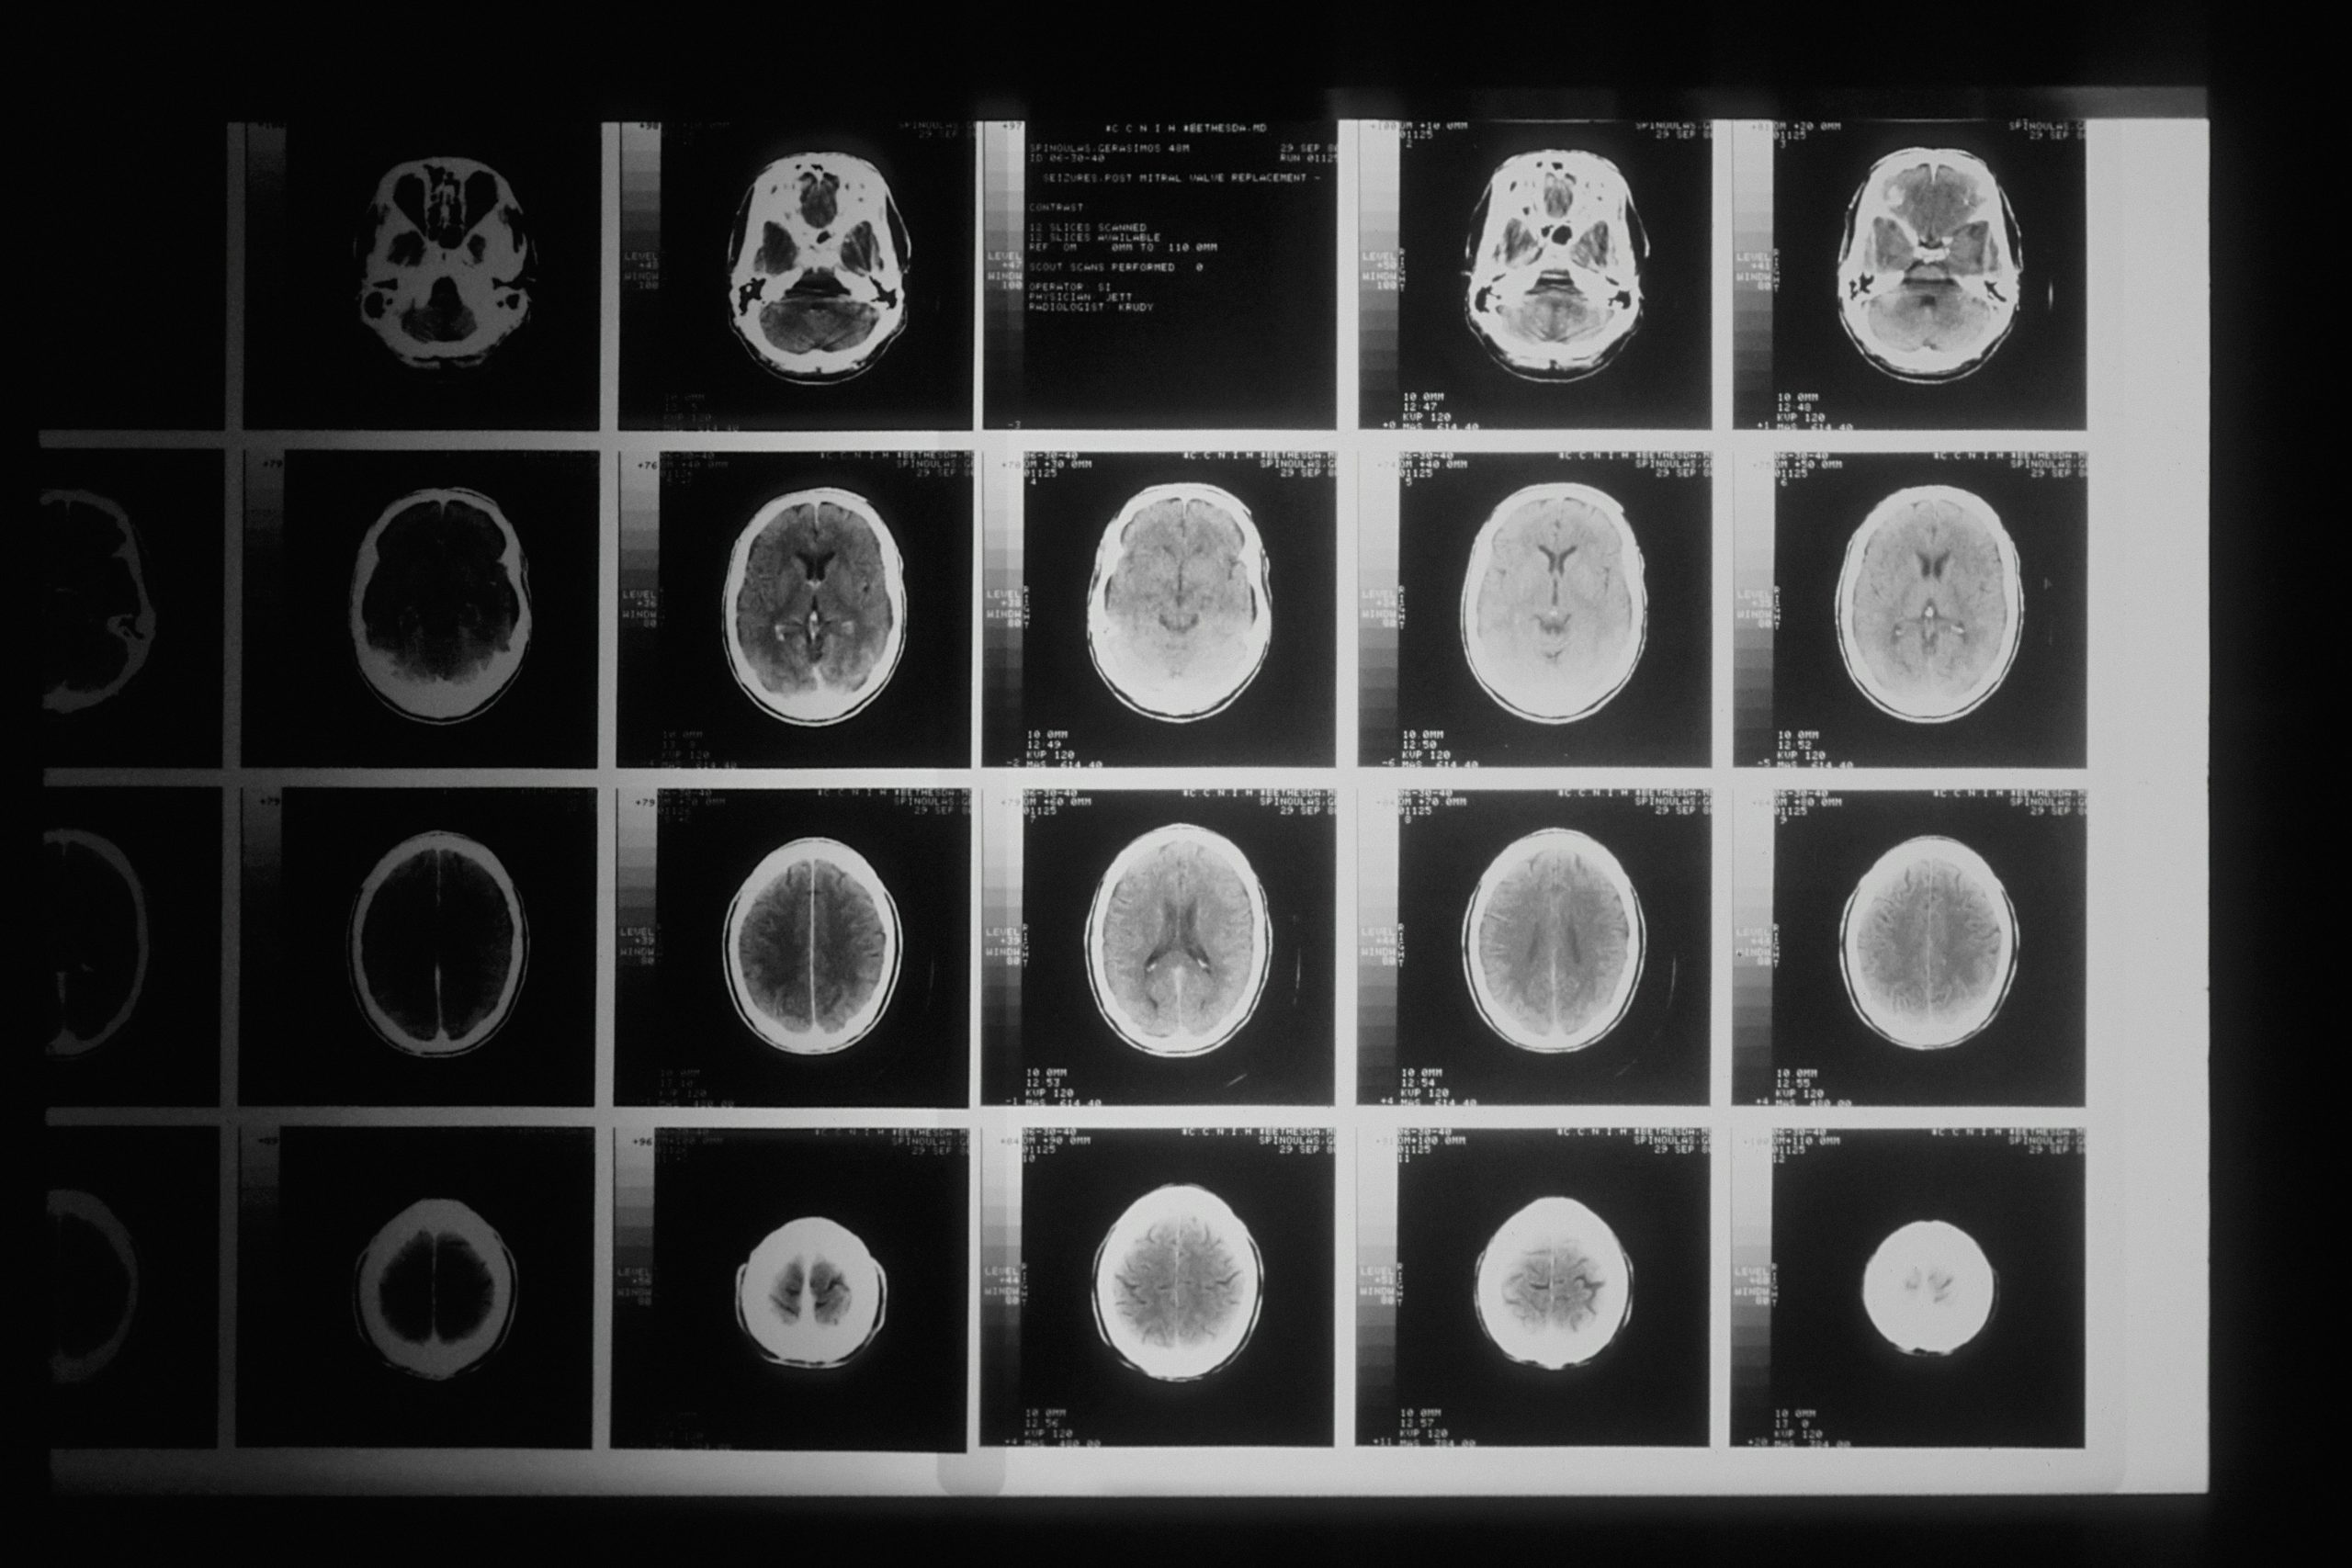

In der Schweiz ist die durchschnittliche Strahlenexposition der Bevölkerung durch medizinische Anwendungen in den letzten 20 Jahren um rund 40 Prozent gestiegen. Hauptgrund dafür ist die zunehmende Zahl von Computertomografie-Untersuchungen.

Angesichts der Auswirkungen ionisierender Strahlung auf die Gesundheit, wurden in der ganzen Schweiz in über 190 Betrieben klinische Audits in den Bereichen Radiologie und Nuklearmedizin, Radiotherapie sowie Kardiologie durchgeführt. Diese haben ergeben, dass die Betriebe beim Strahlenschutz organisatorisch gut aufgestellt sind. Verbesserungspotential gibt es beispielsweise bei der Frage, ob die Untersuchung gerechtfertigt ist oder auch ohne Strahlung möglich wäre.